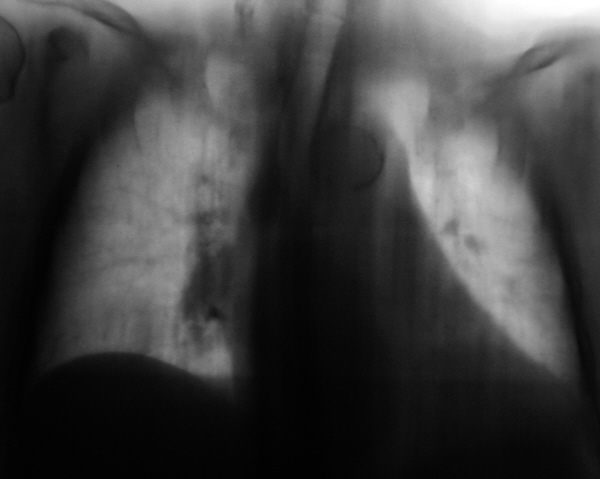

Просвет н/долевого бронха я выделила желтой полосой:

4. Согласна с Андреем Юрьевичем - ателектазов нет. Но на мой взгляд наиболее вероятен распространенный онкологический процесс, вопрос в том, что это: метастазы в легкие и внутригрудные л/узлы без выявленого первичного очага или на их фоне есть первичная опухоль в легком. У меня под подозрением ср/доля правого легкого: